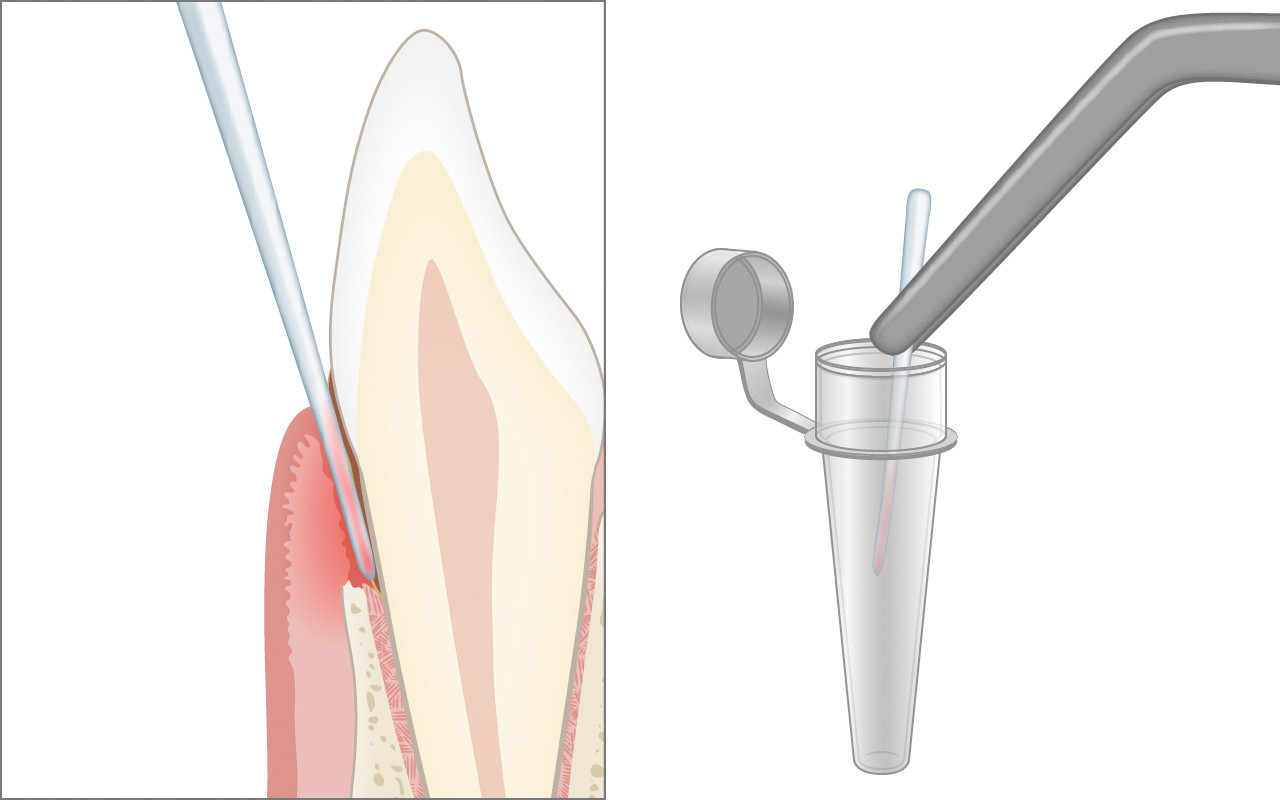

Mikrobiologischer Test

Mikrobiologische Methoden bieten uns heute Zugang zu Informationen, die mit herkömmlichen Testmethoden nicht zu gewinnen waren.

Mit modernen mikrobiologischen Tests wird die Zusammensetzung des Zahnbelags (Plaque) auf folgende schädliche Bakterienarten (Leitkeime) hin untersucht:

- Prevotella intermedia

- Porphyromonas gingivalis

- Agregatibacter actinomycetemcomitans

- Treponema denticola

Die Kosten für diesen diagnostischen Mehraufwand sind dann gerechtfertigt, wenn die gewonnenen Informationen zu einer verbesserten Behandlung führen oder wenn unnötige Behandlungen vermieden werden können.